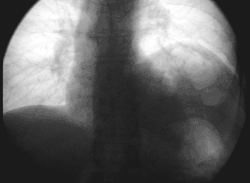

Bei einer Lähmung des Nervus phrenicus erschlafft auf der entsprechenden Seite das Zwerchfell, d. h., es kommt zu einer Zwerchfelllähmung (Zwerchfellparese). Da die Bauchorgane normalerweise durch das Zwerchfell nach unten gedrückt werden, drücken diese bei Erschlaffung des Zwerchfells nach oben. Es entsteht ein sogenannter Zwerchfellhochstand. Ein einseitiger Zwerchfellhochstand ist zwar mit starken Atembeschwerden verbunden, wird aber in der Regel überlebt. Ein beidseitiger Ausfall des Nervus phrenicus ist dagegen lebensgefährlich.